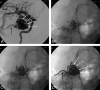

Background and purpose: To report the initial experience by using a new liquid embolic agent (Onyx) for embolization of brain arteriovenous malformations (AVMs).

Methods: Between May 2000 and December 2005, 44 patients with brain AVMs were embolized with Onyx. There were 18 women and 26 men with a mean age of 42.4 years (median 44, range 14-71 years). Clinical presentation included seizures in 26 patients (59%), hemorrhage from the AVM in 13 patients (30%), subarachnoid hemorrhage from a concomitant aneurysm in 3 patients (7%), visual disturbances in 1 patient (2.3%), and in 1 patient (2.3%) the AVM was an incidental finding. Mean estimated size of the AVM was 3.9 cm (median 4, range 2-7 cm).

Results: In 44 patients, 52 embolization procedures were performed with 138 feeding pedicles embolized, ranging from 1 to 7 per patient. Average estimated size reduction was 75% (median 80%, range 40%-100%). Total obliteration was achieved in 7 AVMs (16%), and partial embolization was followed by surgery in 10 patients and by radiosurgery in 20 patients. Complications occurred in 6 patients, leading to death in 1 patient (mortality 2.3%) and to permanent disability in 2 patients (morbidity 4.6%).

Conclusion: Onyx is feasible and safe in the embolization of brain AVMs. Complete obliteration can be achieved in small AVMs. Large AVMs can be adequately reduced in size for additional surgical or radiosurgical treatment.